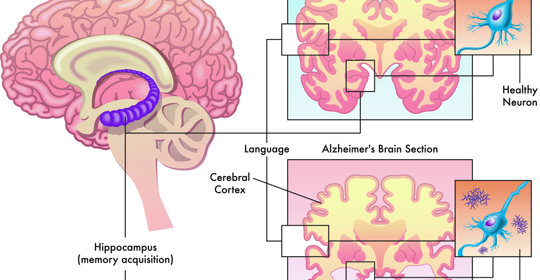

大腦與神經

瀰漫性頭痛:治療方式、診斷方法及預防措施

瀰漫性頭痛:就診科室與常見症狀

瀰漫性頭痛:緩解頭暈的方法

瀰漫性頭痛:檢查專案與診斷方法

劇痛左後腦:原因與處理